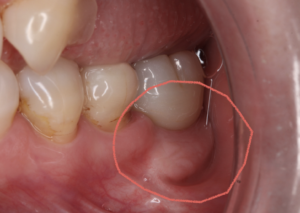

今回はインプラント治療を受けられた60歳代女性についてご報告させていただきます。(掲載の同意を頂いております)

歯を支える骨が痩せてしまう歯周病がレントゲンの右上の赤丸の部位にありました。

また、レントゲン左下の被せ物が取れてしまったという主訴でお見えになりました。

上の歯は、歯の動揺が著しく抜歯を行なったのちにインプラントになりました。

また、取れてしまった部位は歯の崩壊が顕著でこちらも保存が難しく残念ながら抜歯となりました。

インプラントを行う際は、CTを撮影した後に、最新のデジタル診断を行い、可能な限り低侵襲にできるよう骨のある部位を探して、そこにインプラントを入れる計画を立てます。

上顎洞の内側に骨がしっかりありましたので、その部位にガイドを用いて埋入していきます。

こちらがインプラントを入れた後のレントゲンです。

強い歯茎を獲得するために、上顎の口蓋というところから歯茎を移植することもあります。痛みはそこまでありません。

強い歯茎を獲得することで歯ブラシも痛みなくすることができ長い目で見て衛生的です。そして最後のインプラントの歯が入り治療終了です

患者様には12か月ほどお付き合いいただき頑張ってきただきました。今後はインプラントだけでなく天然歯が一生涯持つようにメンテナンスでしっかりフォローしていきたいと思っています。